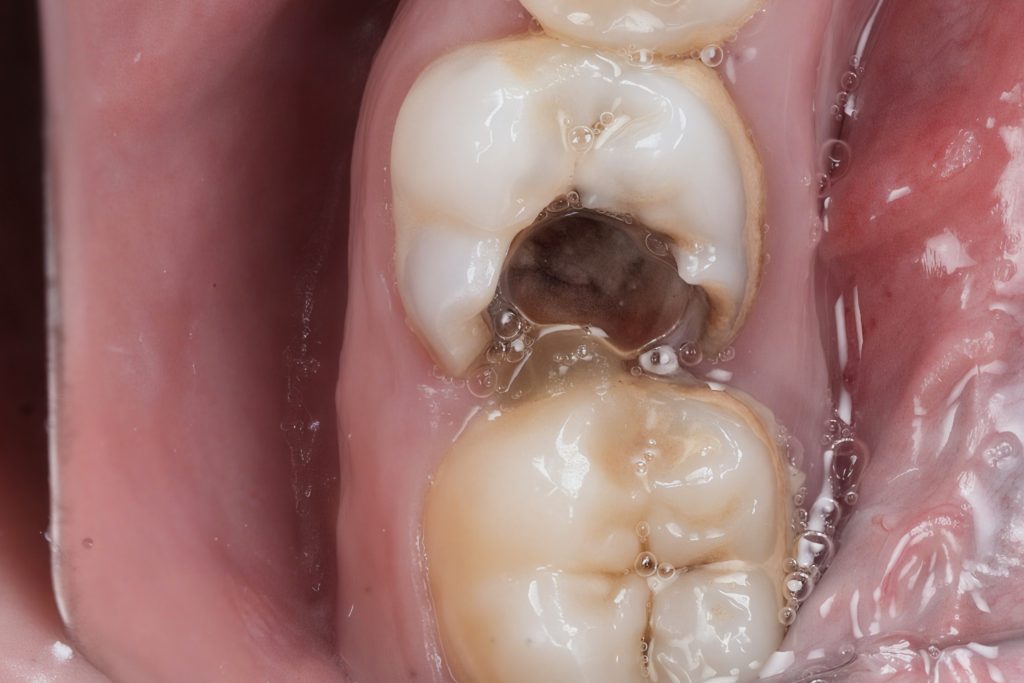

1️⃣ Pre-Operative Assessment

The patient presented with food lodgment and sensitivity over the lower right first molar. Radiograph revealed a deep Class II distal lesion approaching the pulp (Fig 1). Diagnosis: symptomatic irreversible pulpitis.

- Fig 1: Pre-op radiograph showing distal deep caries.